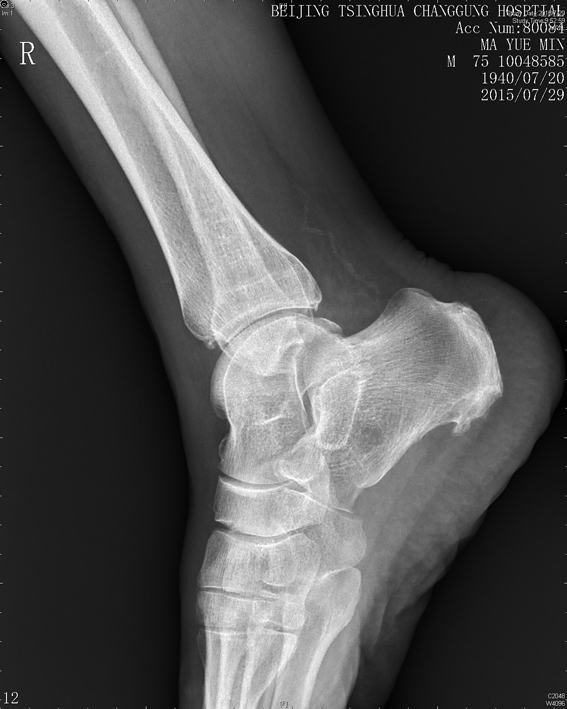

右踝关节X线示:踝关节退行性变。